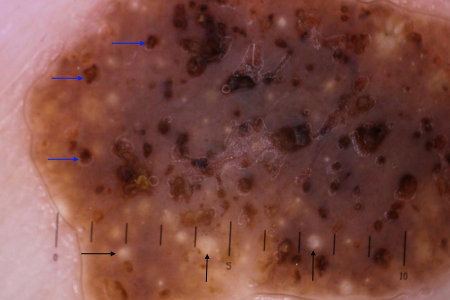

Typical dermoscopic appearance of seborrheic keratosis with milia-like cysts (black arrows) and comedo-like openings (blue arrows)

Primary Care Dermatology Society (PCDS); used with permission